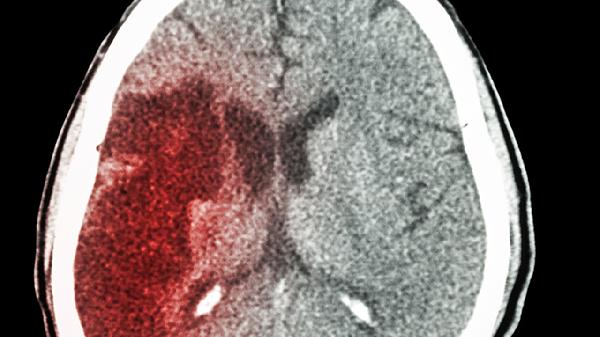

脑室周围出血或蛛网膜下腔出血后,血块阻塞脑脊液通路或引起粘连性改变。出血急性期需控制血压、降低颅内压,慢性期若形成脑积水可考虑脑室腹腔分流术。头部CT能明确出血部位及脑室扩张程度。